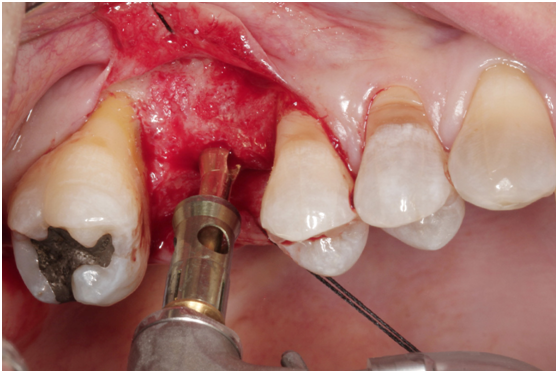

980305幫患者補角化牙齦並翻開清除發炎組織,期待能阻止繼續骨破壞

c. 由98/3補皮的臨床照片,推敲最初原本後面的三顆植體有可能放置在較頰側,但由於鄰接面有足夠的骨頭高度,所以牙齦仍被支撐在恰當位置,因此臨床上無特別發現;但當根裂拔牙後,鄰接面的高度一掉,很快地原本頰側骨頭不足的問題,便很快的浮現出來;接著螺紋跑出,而患者又是牙周病的高風險群,當時身體狀況不佳,口腔衛生照顧不足,都加乘造成骨破壞進一步進行。